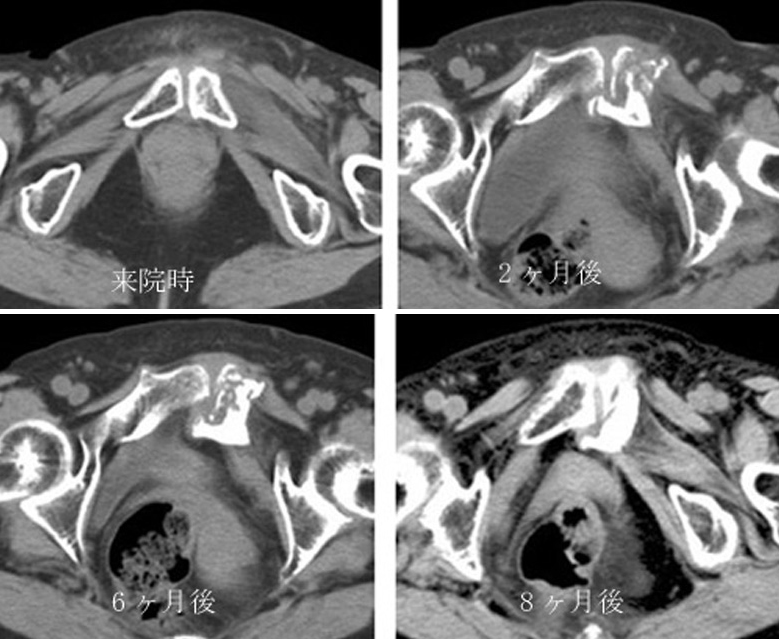

恥骨疲労骨折 恥骨結合炎 古東整形外科 リウマチ科